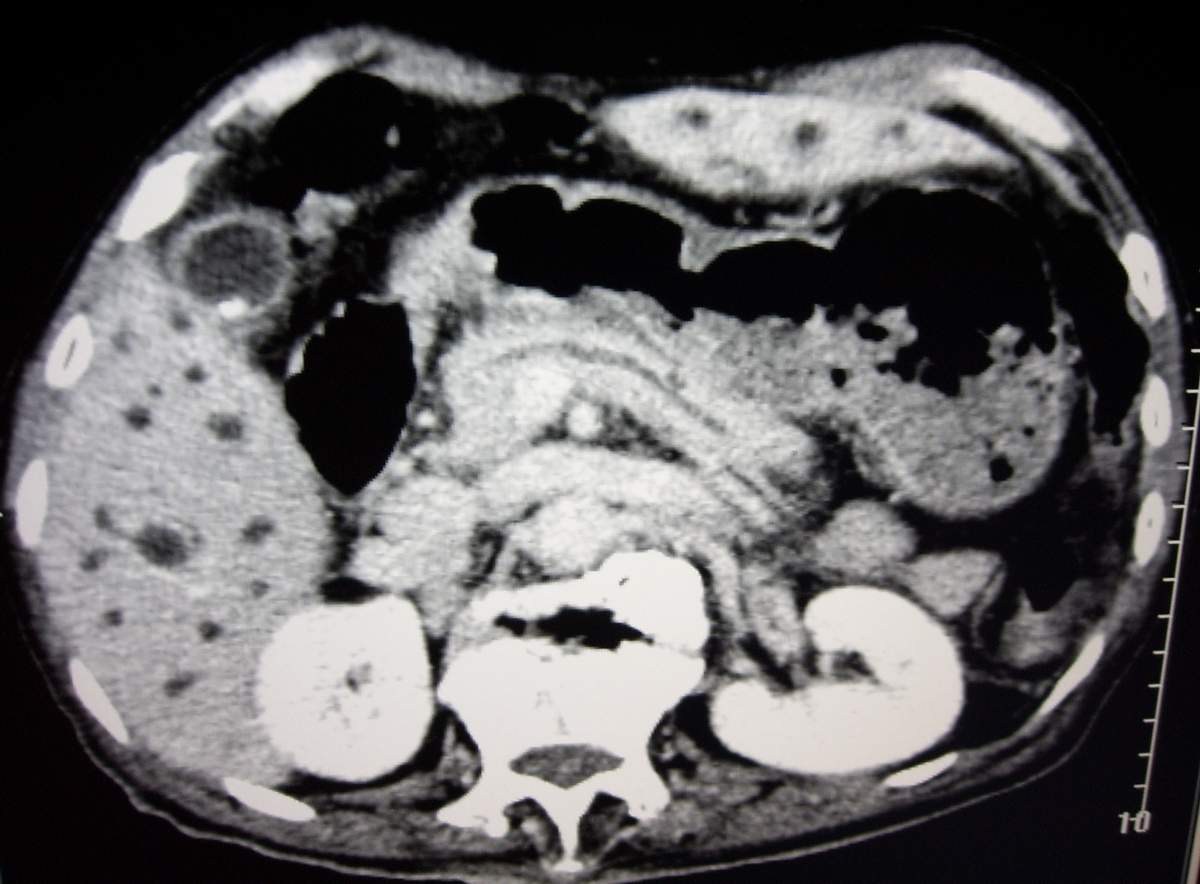

男,77岁,病史不详。

肝内胆管扩张、主胰管扩张 ,胰头影大,考虑胰头癌或胆管下端癌侵犯胰腺可能性大

建议mrcp检查。

慢性胆囊炎,胆结石,左肾囊肿,胰头癌伴肝内胆管、胰管扩张,不除外侵犯肠系膜上静脉的可能。

肝内外胆管明显扩张,肝门区见软组织密度肿块,胆囊壁增厚,胆囊扩大。胰头不大。考虑:肝门区胆管细胞癌。

肝内胆管扩张明显,cbd未见明显扩张,胰管轻度扩张,肝门部胆总管癌?

1肝门区域软组织影,肝内胆管明显扩张,胰管轻度扩张。考虑肝门区胆管细胞癌。2胆囊结石。3左肾小囊肿。

1 肝内外胆管扩张,肝内明显,胰管扩张,胰头明显增大,符合胰头癌双管征。2 胆囊壁略增厚,胆囊内可见高密度结石影,胆囊炎、胆结石3 左肾囊肿